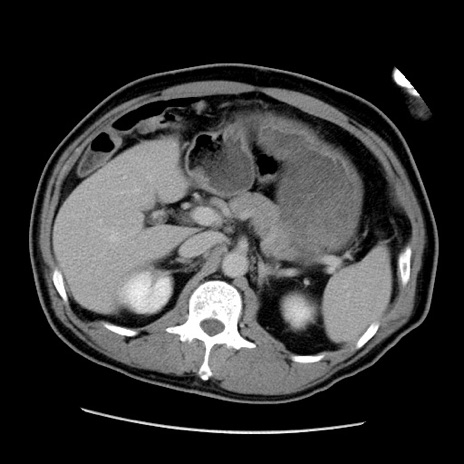

症例22(横断像)

【症例】50歳代男性

【主訴】腹痛

【現病歴】AVMからの被殻出血のため回復期リハ病棟入院中。 本日午後3時頃急に下腹部痛が出現した。

【既往歴】AVM、被殻出血、虫垂炎、高血圧

【身体所見】意識晴明、左半身不全麻痺、会話の理解は良好、36.5°C、腹部:膨隆、全体に板状硬、下腹部正中に圧痛点あり、反跳痛-、筋性防御不明、右下腹部にope scar

【データ】WBC 9400、CRP 0.06